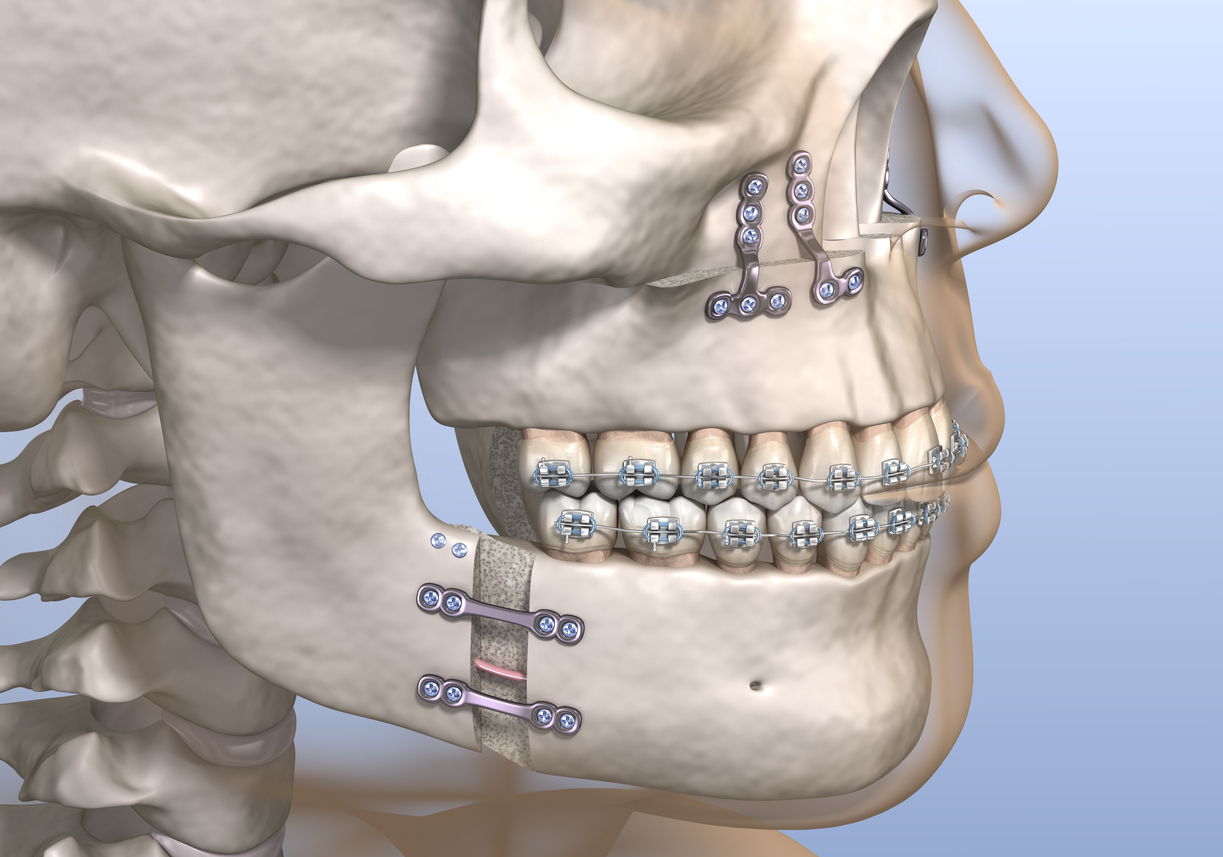

What kind of surgery??You Need surgery

BimaxWhat kind of surgery??

Rhino Ipd bimax just love yourself @haryanvi_incel @PEENO08